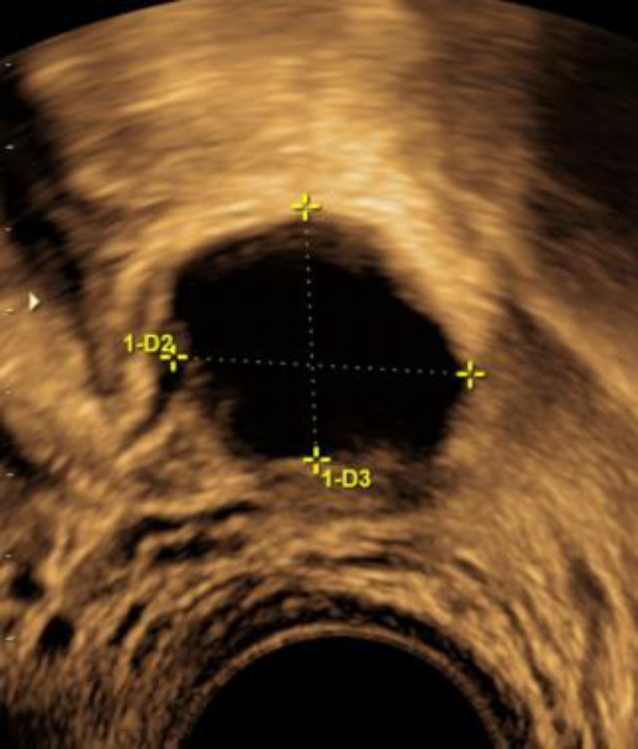

Man begann dann mit einem Zyklusmonitoring. Sonographisch war das Ovarialgewebe in der Peritonealtasche links kaum von einem richtigen Ovar zu unterscheiden (s. Abb. 2).

Abb. 2

Wachsender Leitfollikel im retransplantierten Ovarialgewebe der Fossa ovarica links